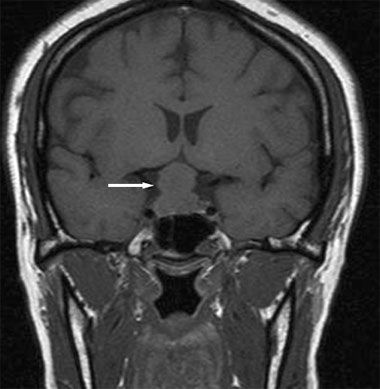

A 26-year-old woman at 30 weeks’ gestation presented to the emergency department with a throbbing frontal headache of 1 month ’s duration. She had also had peripheral blurred vision for the past 2 weeks. Acetaminophen initially decreased her pain but was no longer effective. She had had a previous miscarriage.